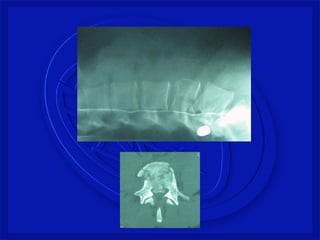

FRATURA COMPRESSÃO TORÁCICA

BAIXA

FRATURA COM LUXAÇÃO COMPLETA –

TORÁCICA BAIXA

As lesões ocorrempor: -Flexão, extensão, rotação, compressão por impacto axial ou combinação desses mecanismos. Mecanismo de Trauma Raqui- Medular com fratura

FRATURA COM LUXAÇÃOCOMPLETA – TORÁCICA BAIXA